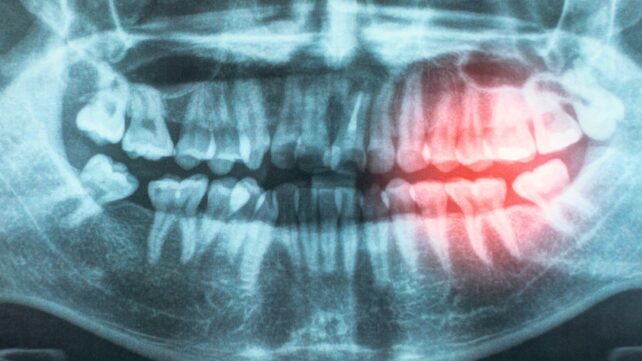

As part of their review, the researchers explored possible reasons for the association, including the likelihood that bacteria enter the body through exposed and damaged gums, contributing to chronic inflammation.

"Gum disease and poor oral hygiene can allow bacteria to enter the bloodstream, causing inflammation that may damage blood vessels and increase the risk of heart disease."